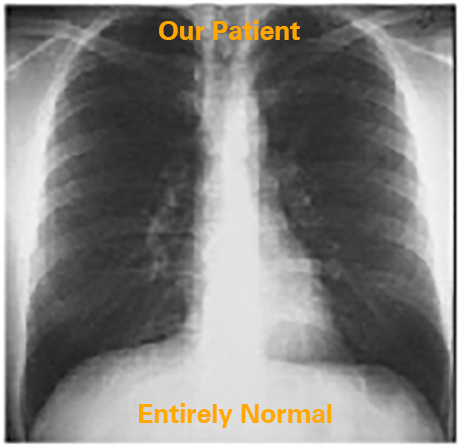

Let us analyze the borders of the cardiac silhouette beginning with the PA view.

The terms right and left always refer to the patient's right and left side. The right border consists of the aortic arch, the superior vena cava and the right atrium inferiorly. The left border consists of the ascending aorta, the main pulmonary artery, the left atrial appendage that is best seen in pathologic circumstances, and the left ventricle that comprises the most inferior portion.